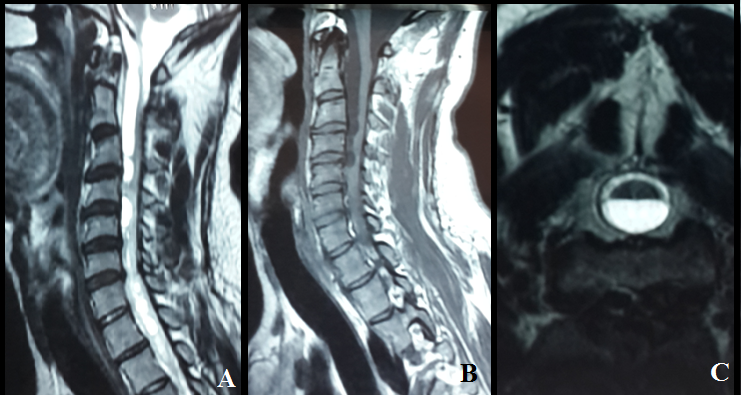

Syringomyelia is a rare condition in which a cyst forms within your spinal cord, secondary syringomyelia following Tuberculousis is very rare. In the present paper, we report a case of tuberculous meningoencephalitis in a 30 year-old Morrocan male complicated six months after under anti-bacillary treatment by progressive quadriplegia due to granulomatous arachnoiditis. The spinal MRI showed an extensive complex syrinx within the cervical and thoracic cord same signal intensity as the cerebrospinal fluid. Arachnoiditis appeared to be the underlying mechanism in these late-onset cases. The availability of MRI has greatly improved our ability to both diagnose and follow these collections. Surgery is the only viable treatment for syringomyelia. The possibility of developing syringomyelia should be always considered in any patient with a history of central nervous system infection.